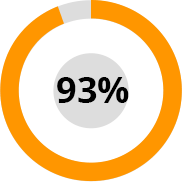

Hogyan segített a HondroLife 2500 tanulmányi résztvevőnek?

Az ízületi betegségek megelőzésének világszervezeti nemzetközi kutatóközpontok hat hónapon át elvégeztek számos klinikai vizsgálatot és alapkutatást a HondroLife spray készítményen. 2500 önkéntes vett részt a kutatásban.

A tesztek eredményeként kiderült: